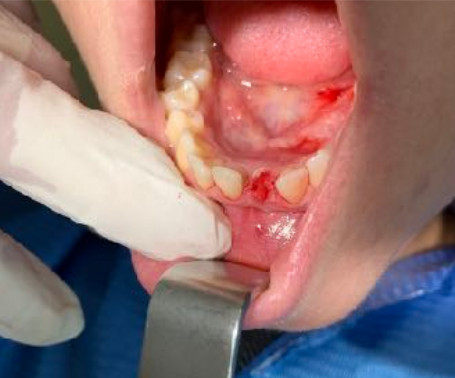

1 - AN INCISIVE CASE

Fracture of lower incisor element 31 and implant rehabilitation